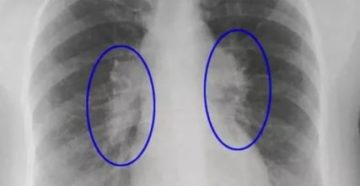

Что такое фиброз легких и почему он может появиться после пневмонии? Диагностика и лечение В…